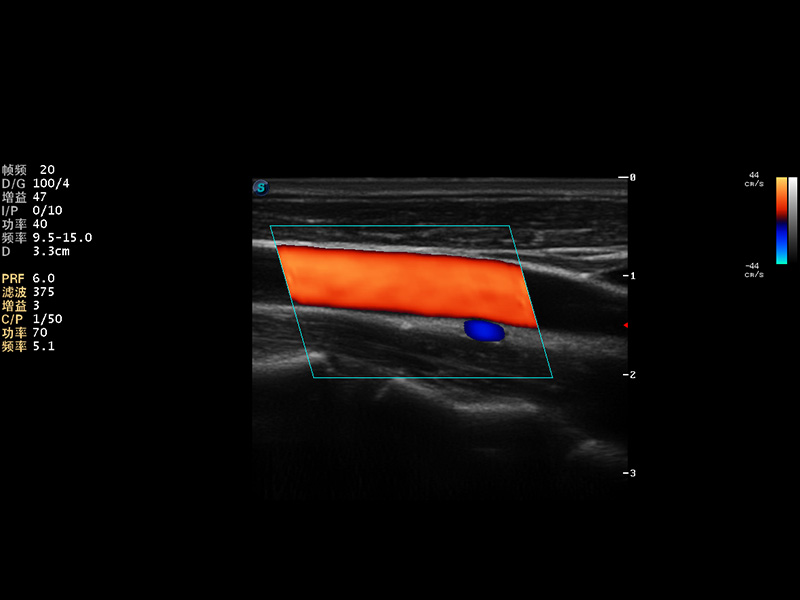

S9便携式彩色多普勒超声诊断仪是16877太阳集团研发的高端便携彩超设备,外观设计新颖、产品性能卓越。S9在便携超声领域采用了突破传统的触摸屏交互设计,并以先进的软件硬件技术和设计理念,为您带来清晰的图像质量、稳定的工作性能和便捷的操作体验。

AutoC智能血流追踪